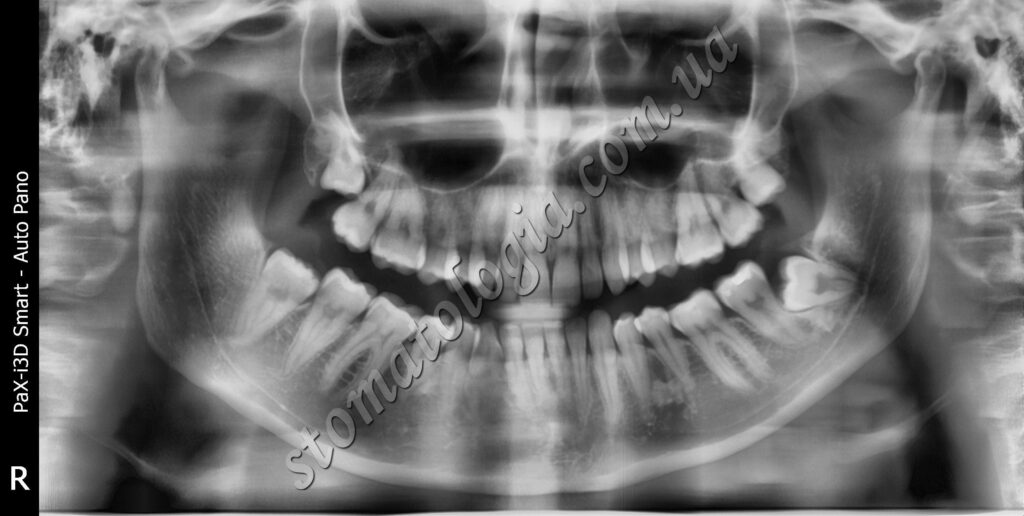

Ретинований зуб мудрості зліва травмує сусідній зуб. Показано видалення зубів мудрості